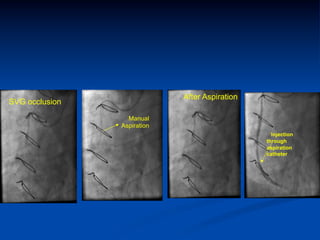

After Aspiration

SVG occlusion

Manual

Aspiration

Injection

through

catheter

After Aspiration SVG occlusion Manual Aspiration Injection through aspiration catheter